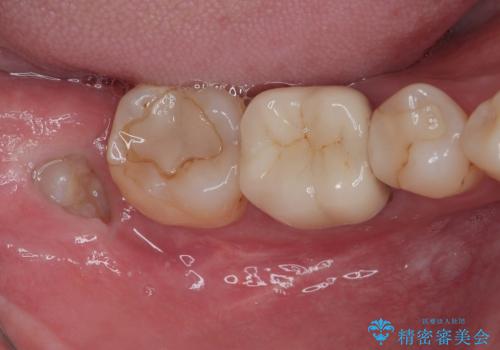

銀歯をセラミックにしたい オールセラミッククラウン

担当医 有澤哲郎